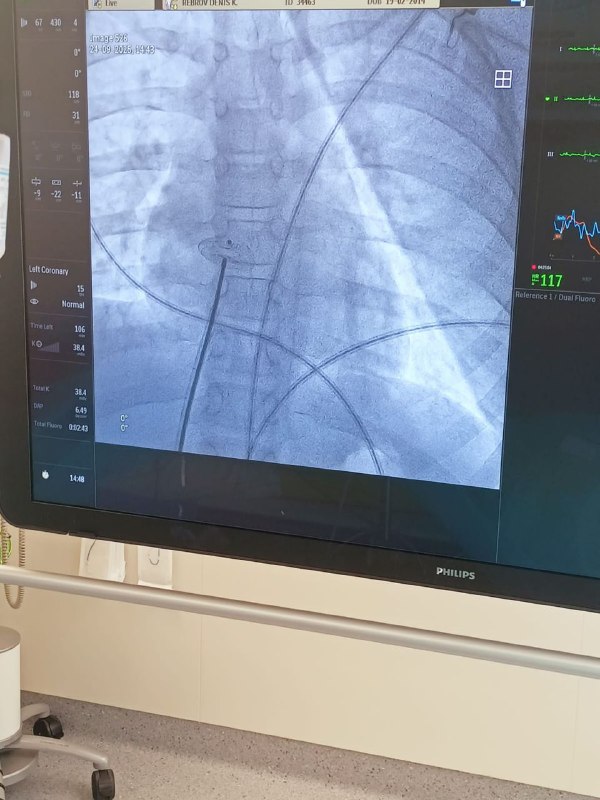

А в августе кардиохирурги выдержали серьезное испытание. Один за одним родились дети с тяжелым, несовместимым с жизнью без операции, пороком сердца. Хирургическое лечение таких врожденных патологий зачастую проходит в два этапа. Первый – т.н. операция Рашкинда, которая проводится буквально в первые сутки жизни малышей и позволяет стабилизировать состояние новорожденных, выполнить дополнительное обследование и лечение, подготовить их к сложной «открытой» операции, во время которой хирурги практически «заново перекраивают» сердце.

Вот этот первый этап хирургического лечения проводится малотравматичным, щадящим методом. Врачи успешно выполнили операции первого этапа в рентген-операционной. Данные операции являются экстренными и, конечно, сложны и психологически, и технически (в силу того, что проводятся они новорожденным детям), а это всегда требует особой филигранности работы всей команды. Если же учесть, что все малыши появились на свет в относительно короткий период времени, и потребовалось выполнить им этапные операции тоже в короткий период, одну за одной, с интервалом несколько дней, - известное напряжение у кардиохирургов присутствовало.